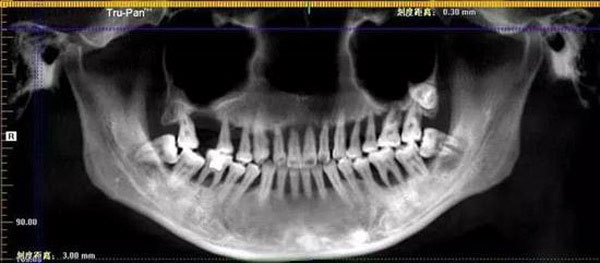

07/01/2019 16:16Cô gái 28 tuổi rụng răng, móm mém như cụ bà 80 vì thói quen xấu

Gần đây, bệnh viện nha khoa Hàng Châu vừa tiếp nhận một bệnh nhân nữ, Tiểu Manh, 28 tuổi, bị rụng răng cửa khi đang đánh răng. Sau khi khám xét, bác sĩ kết luận cô bị viêm nha chu nặng và phải nhổ bỏ toàn bộ hàm răng trên. Như sét đánh ngang tai, Tiểu Manh ngồi lặng người trong phòng khám 20 phút, sốc không nói nên lời.

Tiểu Manh chia sẻ, trước khi bị rụng răng cửa, cô đã biết hàm răng của mình rất xấu và yếu. Trong suốt 6 năm qua, răng của cô lung lay theo từng ngày, chân răng lộ ra. Đã từ rất lâu Tiểu Manh không biết đến mùi vị của thịt vì không thể nhai, cô hầu như chỉ có thể ăn thức ăn mềm, nhão hoặc uống nước canh.

Với tình trạng trên, Tiểu Manh không những không chữa trị, mà còn cho rằng việc răng đau có thể giúp cô giảm béo và trở nên xinh đẹp hơn. Cho đến khi hai chiếc răng cửa rụng xuống, Tiểu Manh mới bắt đầu ý thức được mức độ nghiêm trọng.

Bác sĩ Lý Trí - người điều trị trực tiếp cho Tiểu Manh cho biết, cô đã mắc viêm nha chu từ 6 năm trước, tuy nhiên chủ quan không chữa trị một cách triệt để.

Mặc dù Tiểu Manh có thói quen vệ sinh răng hai lần một ngày vào buổi sáng và buổi tối nhưng lại không chú ý đến cách chải răng đúng cách, khiến thức ăn thừa không được lấy hết ra khỏi kẽ răng. Ngoài ra, Tiểu Manh còn không sử dụng chỉ nha khoa và nước súc miệng cho khiến tình trạng bệnh càng thêm nặng.

Với tình hình hiện tại, răng của Tiểu Manh hầu như không thể tiếp tục sử dụng mà phải nhổ bỏ và trồng răng mới thay thế. Qua đây, bác sĩ Lý cũng đưa ra lời khuyến cáo cho mọi người, khi có các dấu hiệu như chảy máu chân răng, sưng, viêm lợi cần lập tức đi kiểm tra vì đó có thể là dấu hiệu của bệnh viêm nha chu.